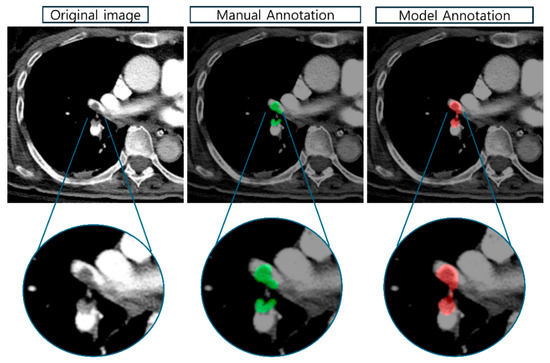

Multi-Task Deep Learning for Lung Nodule Detection and Segmentation in CT Scans

The early detection of pulmonary nodules in chest CT scans is critical for improving lung cancer outcomes. While existing computer-aided diagnosis (CAD) systems have shown promise, most treat detection and segmentation as separate tasks, leading to fragmented pipelines and limited representation sharing. This [...] Read more.

The early detection of pulmonary nodules in chest CT scans is critical for improving lung cancer outcomes. While existing computer-aided diagnosis (CAD) systems have shown promise, most treat detection and segmentation as separate tasks, leading to fragmented pipelines and limited representation sharing. This study proposes a 2.5D multi-task learning (MTL) framework that integrates both tasks within a unified Mask R-CNN architecture. The framework incorporates a tailored preprocessing pipeline—including Hounsfield Unit (HU) normalisation, CLAHE enhancement, and lung parenchyma masking—to improve input consistency and task-relevant contrast characteristics. To enhance sensitivity for small or ambiguous nodules, an auxiliary RoI classifier is introduced. Additionally, a nodule-level evaluation strategy aggregates slice-wise predictions across the z-axis, supporting a clinically meaningful assessment that approximates 3D diagnostic workflows. Experiments on the LUNA16 dataset demonstrate that the proposed framework achieves a favourable trade-off between detection and segmentation performance under a unified 2.5D multi-task setting. These results highlight the potential of integrated MTL approaches to advance CAD systems for early lung cancer screening. Full article